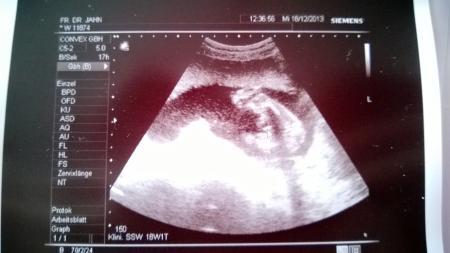

...... ein JUNGE ... Beweisbild hängt dran. Die Ärztin meinte falls es Abfällt sagt sie Bescheid. Nun gut dann wächst die Jungsrunde hier halt um noch ein Mitglied. Ich freu mich. Und der Papa der eigentlich gern ein Mädchen gehabt hätte freut sich auch über einen Jungen. Nun muss ich das nur noch meinem noch Jüngsten beibringen das es ein Brüderchen wird und kein Schwesterchen wie er sich gern gewünscht hätte. Leider kann ich euch nur sagen das er einen großen Fuß schon hat. 2,9 cm. Davon hab ich auch ein Bild. Er war sehr aktiv nachdem die Ärztin ihn etwas geärgert hat damit er mal die Beinchen öffnet. Das erfreulichste allerdings ist das der Cervix bei schönen 4,9 cm liegt. Daher ist momentan nichts von einer Insuffienz zusehen.

Die Bilder sind ja so klein. Ich lad sie nochmal einzeln hoch.